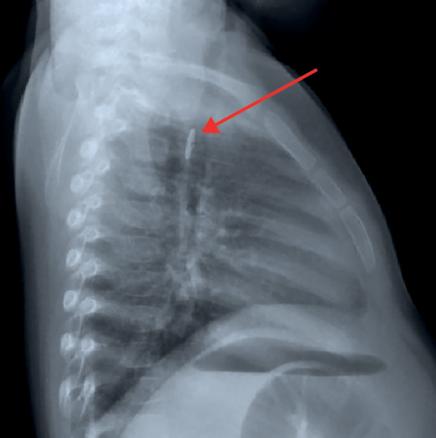

Chez l’enfant, les jouets ou leurs composants (notamment des piles boutons, fig. 2) et les pièces de monnaie sont en cause dans 50 à 70 % des cas, mais provoquent rarement des blessures profondes ou perforantes. Dans la population adulte, les « intrus » sont souvent alimentaires (os, arêtes, viande… chez deux tiers des sujets) ; parfois, il s’agit d’objets plus volumineux (prothèse dentaire, comme chez cette patiente) ou plus acérés (cure-dent, épingles…).

Le bilan radiologique comporte des clichés cervicaux, thoraciques et éventuellement un abdomen sans préparation. En cas de CE radio-opaque (objet métallique, pièce de monnaie...), il permet de déterminer sa taille, sa nature et sa localisation, de dépister d’éventuelles complications et de surveiller sa progression dans le tube digestif. Il n’est pas systématique en cas d’incarcérations d’aliments dans la muqueuse digestive.